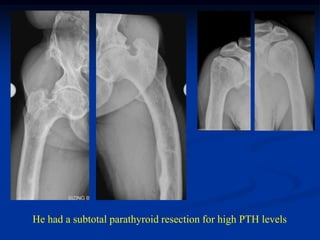

Case #3    X-linked hypophosphatemic Osteomalacia

54 yr 5’2” male with low serum P and life time of universal bone pain

He had a subtotal parathyroid resection for high PTH levels

Case #3 X-linked hypophosphatemic Osteomalacia 54 yr 5’2” male with low serum P and life time of universal bone pain

He had asubtotal parathyroid resection for high PTH levels